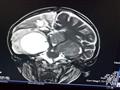

"خدي ابنك في حضنك واشبعي به"..هكذا قال أطباء لوالدة الطفل يحي محمد يحيي، ابن محافظة بورسعيد، صاحب الـ11 عام، بعدما تدهورت حالته الصحية، ونتج عنها فقدان لحاستي السمع والبصر بالكامل

حاولت والدة يحبي التمسك وحبس دموعها التى تساقطت أكثر من مرة أثناء روايتها لمأساة ابنها، قائلة :"ابني يعاني من ورم سرطاني خيث في المخ، منذ شهر يوليو من العام الماضي، وذهب به إلي مستشفي (57357) لعلاج سرطان الأطفال، لكنهم رفضوا استقبال حالته، وأرسلوني إلي مستشفي (أبو الريش)، وهناك تم إجراء عمليتين لابني، الأولي للأورام في 29 يوليو، والثانية في الصمام في 31 أغسطس من نفس العام، وبعد إجراء العمليتين بدء سمع ونظر ابني يقل تدريجيًا، وعندما ذهبت للأطباء للاستفسار عن سبب تدهور حالة ابني.

أجمع الأطباء على ضرورة عرض حالة يحيي علي طبيب مخ وأعصاب، وعندما ذهبت إلي طبيب المخ والأعصاب المعالج له، والذي أجري له العملية الجراحية، أخبرني بعدم وجود أخطاء في العملية ، وانه لا يعرف سبب المشكلة".

وتابعت حديثها :"ذهبت إلي أطباء أخرين وطالبوني بعمل اشاعات أخري، وتبين منها أن الورم عاد من جديد علي جذع المخ، وعندما ذهبت به إلي مستشفي أبو الريش مرة أخري، أخبروني أن حالة ابني علاجها في معهد الأورام فذهبت إلي المعهد وهناك كان من المفترض أن يحصل ابني علي من 25 إلي 30 جلسة، لكنهم اختصروها إلي 10 جلسات فقط، وبعد انتهاء الـ10 جلسات فوجئت بابني يفقد اسمع والبصر نهائيًا، بجانب أن الجزء الشمال من جسمه لا يتحرك، فابني أصبح يأكل بكميات قليلة جدًا، أي أنه شبه ممتنع عن الأكل، ولم يفيدني أي طبيب حتي الأن بحالة ابني، وقالوا لي :"خدي ابنك في حضنك واشبعي بيه فحالته صعبة".